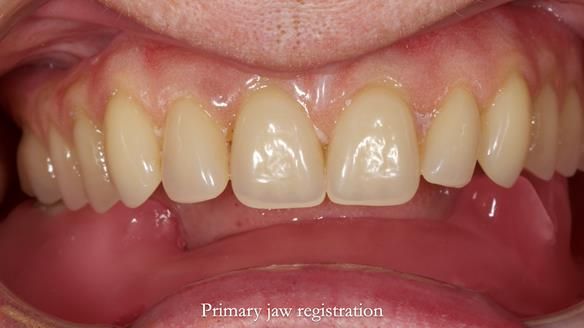

Mary’s upper occlusal plane wasn’t parallel to her interpupillary line, and she specifically wanted that natural asymmetry preserved. Rowan arranged the teeth beautifully, following the exact contour and character of her original smile.

For both the upper and lower dentures, we used Schottlander Enigma Life teeth. I’ve been using these since 2014 and they’ve been outstanding - the surface texture, colour depth, and light reflection are superb. When arranged to mirror the patient’s natural tooth positions, they look completely lifelike.